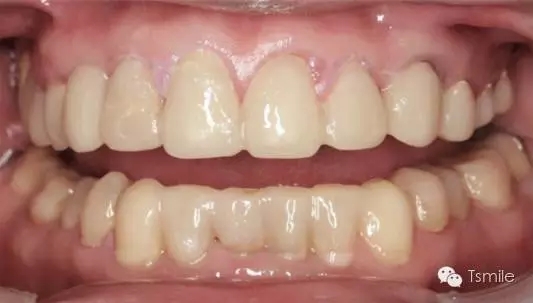

例如面對一個牙列重度磨耗的美學(xué)修復(fù)患者,我們首先根據(jù)患者主訴和美學(xué)檢查形成美學(xué)設(shè)計,然后通過數(shù)碼圖像表達(dá)美學(xué)設(shè)計思想,制作診斷蠟型,口內(nèi)制作診斷飾面,更加真實地表達(dá)美學(xué)設(shè)計。根據(jù)患者的要求和口內(nèi)試戴情況調(diào)改診斷飾面,最終確定美學(xué)修復(fù)設(shè)計,即最終修復(fù)體的各種美學(xué)參數(shù)。接下來就是美學(xué)實現(xiàn)過程,在診斷飾面上進(jìn)行精確地牙體預(yù)備,制取印模和工作模型,技師按照最終診斷飾面的形態(tài)、大小和排列制作最終美學(xué)修復(fù)體,最后完成修復(fù)體粘接。

前兩個美學(xué)分析和美學(xué)表達(dá)過程已經(jīng)確定了患者滿意的最終的美學(xué)修復(fù)設(shè)計,也就是已經(jīng)確定了最終修復(fù)體的形態(tài)、大小、排列、牙齦曲線等各種美學(xué)參數(shù),美學(xué)實現(xiàn)就是復(fù)制前面已經(jīng)確定的美學(xué)設(shè)計的過程,包括牙體預(yù)備、印模制取、修復(fù)體制作、修復(fù)體試戴粘接等過程。